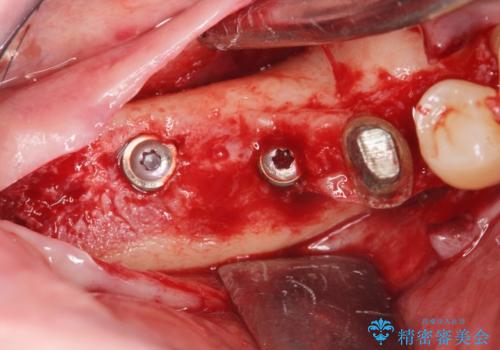

長期的な予後の見込めない奥歯の抜去を行い、骨と歯ぐきの治癒を待ち、インプラント治療を計画します。

インプラント周囲には骨の増生を埋入時に同時に行っています。